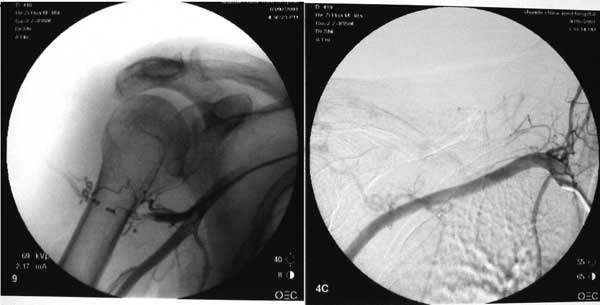

女性,38岁。一年前右肩部包块在外院诊断为“动脉瘤”,介入后手术切除。术后伤口愈合良好,但右肩关节活动欠灵活,右肩上举困难。半年前再次出现包块,无疼痛,今收入院。体检:右肩部有12cm横向切口疤痕,疤痕边缘扪及大拇指头大小的包块,边界不清,可扪及搏动。右肩峰处有小柿子大小的包块,界限不清,呈囊性,亦可扪及搏动。

经右侧股动脉穿刺,将导管通过腹主动脉、胸主动脉、无名动脉超选入右侧锁骨下动脉,造影示肩部软组织大量动脉血管丛存在,主要供血分支由胸肩峰动脉和旋肱后动脉提供。

以超选择进入供血分支,并将其采用海绵、钢圈闭塞,造影证实血管瘤供血动脉完全阻断。